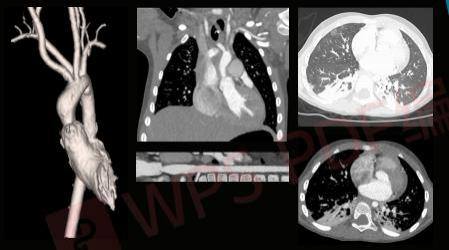

无镇静剂下儿童CTA扫描图像

APEX CT在心脏检查方面,完全革新了以往的复杂检查流程:不需要控制心率,不受心律变化影响,甚至不需要控制呼吸。患者完全在自然状态下接受检查,只需在一个心跳内就完成了整个心脏 CT扫描,这对疑难冠脉病变、血管变异、先天性心脏病等疾病的治疗,都有着重要的意义。

不仅如此,APEX CT对微小病灶的检出能力也显现出无与伦比的优势。传统 CT 扫描心脏冠脉,只能看到一级二级的血管,而 APEX CT可以看到三级、四级,甚至更小的分支;传统CT对直径1毫米以下的血管很难拍出清晰图像,而 APEX CT却可以做到,这意味着能看到更多的微小病灶。